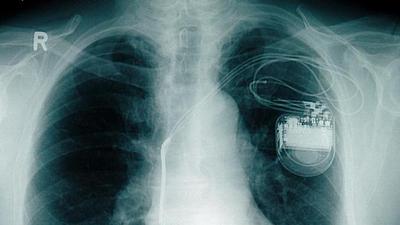

marcapasso.jpg

Marca-passo sem bateria é testado com sucesso em porcos

26/04/2019, 07:25

Dispositivo obtém energia a partir dos próprios batimentos cardíacos. Caso funcione em seres humanos, invenção pode representar um grande alívio para pacientes com o implante.